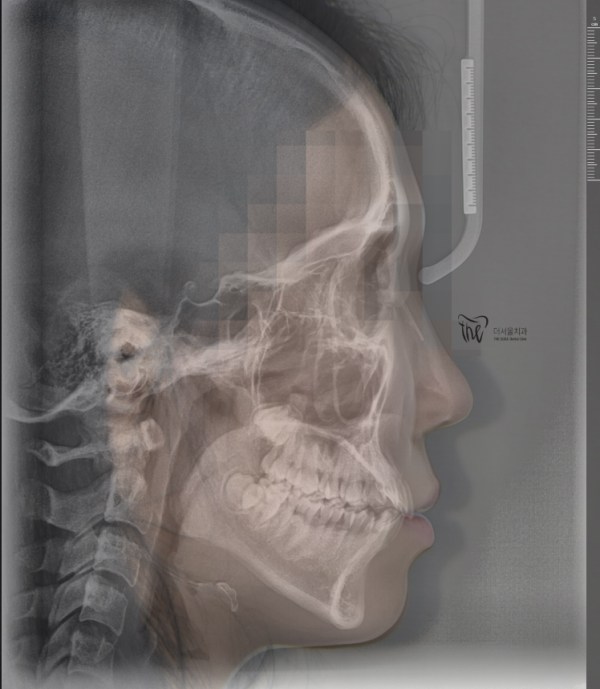

이렇게 측면 사진에서도

앞니들이 앞으로 뻐드러져 있는것을 확인할 수 있습니다.

Even in the side picture

You can see that the front teeth are protruding forward.